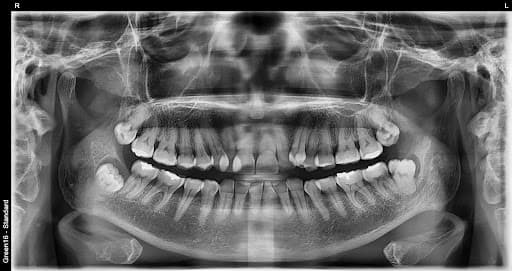

横生智齿

横向生长会挤压 相邻的牙齿

复杂的阻生智齿 - 即使深埋在牙龈中也没问题

贴近神经的智齿 - 无需担心神经损伤,安全拔除

水平阻生智齿 - 即使是横向生长的困难案例也可以处理